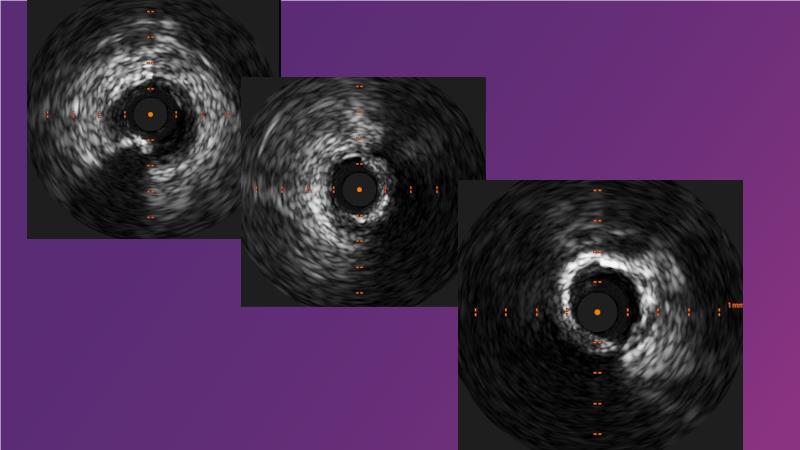

Sirolimus-coated balloon: expanding the scope of indications for complex coronary artery disease treatment

Watch this session to gain case-based insights on using DCBs in complex settings. Learn valuable tips and tricks for optimal DCB application, including the best timing and situations for their use. Discover how to effectively implement a hybrid strategy that combines DES and DCB when needed.